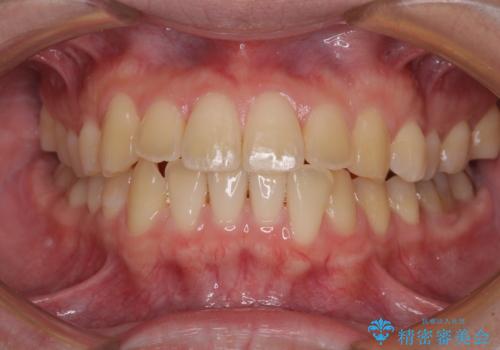

【モニター】前歯のクロスバイトと隙間を改善 インビザラインによる矯正治療

- 前歯のクロスバイトを気にして来院された患者様です。

骨格的には問題がなかったため、インビザラインを用いて咬み合わせを改善していくこととしました。

インビザライン特有の、奥歯の咬み合わせの問題もなく、しっかりと歯列を改善することができました。

舌側転位している上顎側切歯(内側に引っ込んでいる真ん中から2番目の歯)は、インビザラインが最も移動を苦手とする歯であり、これ以上の改善を望まれる場合にはワイヤー矯正、あるいはワイヤー矯正の併用をお勧めいたします。